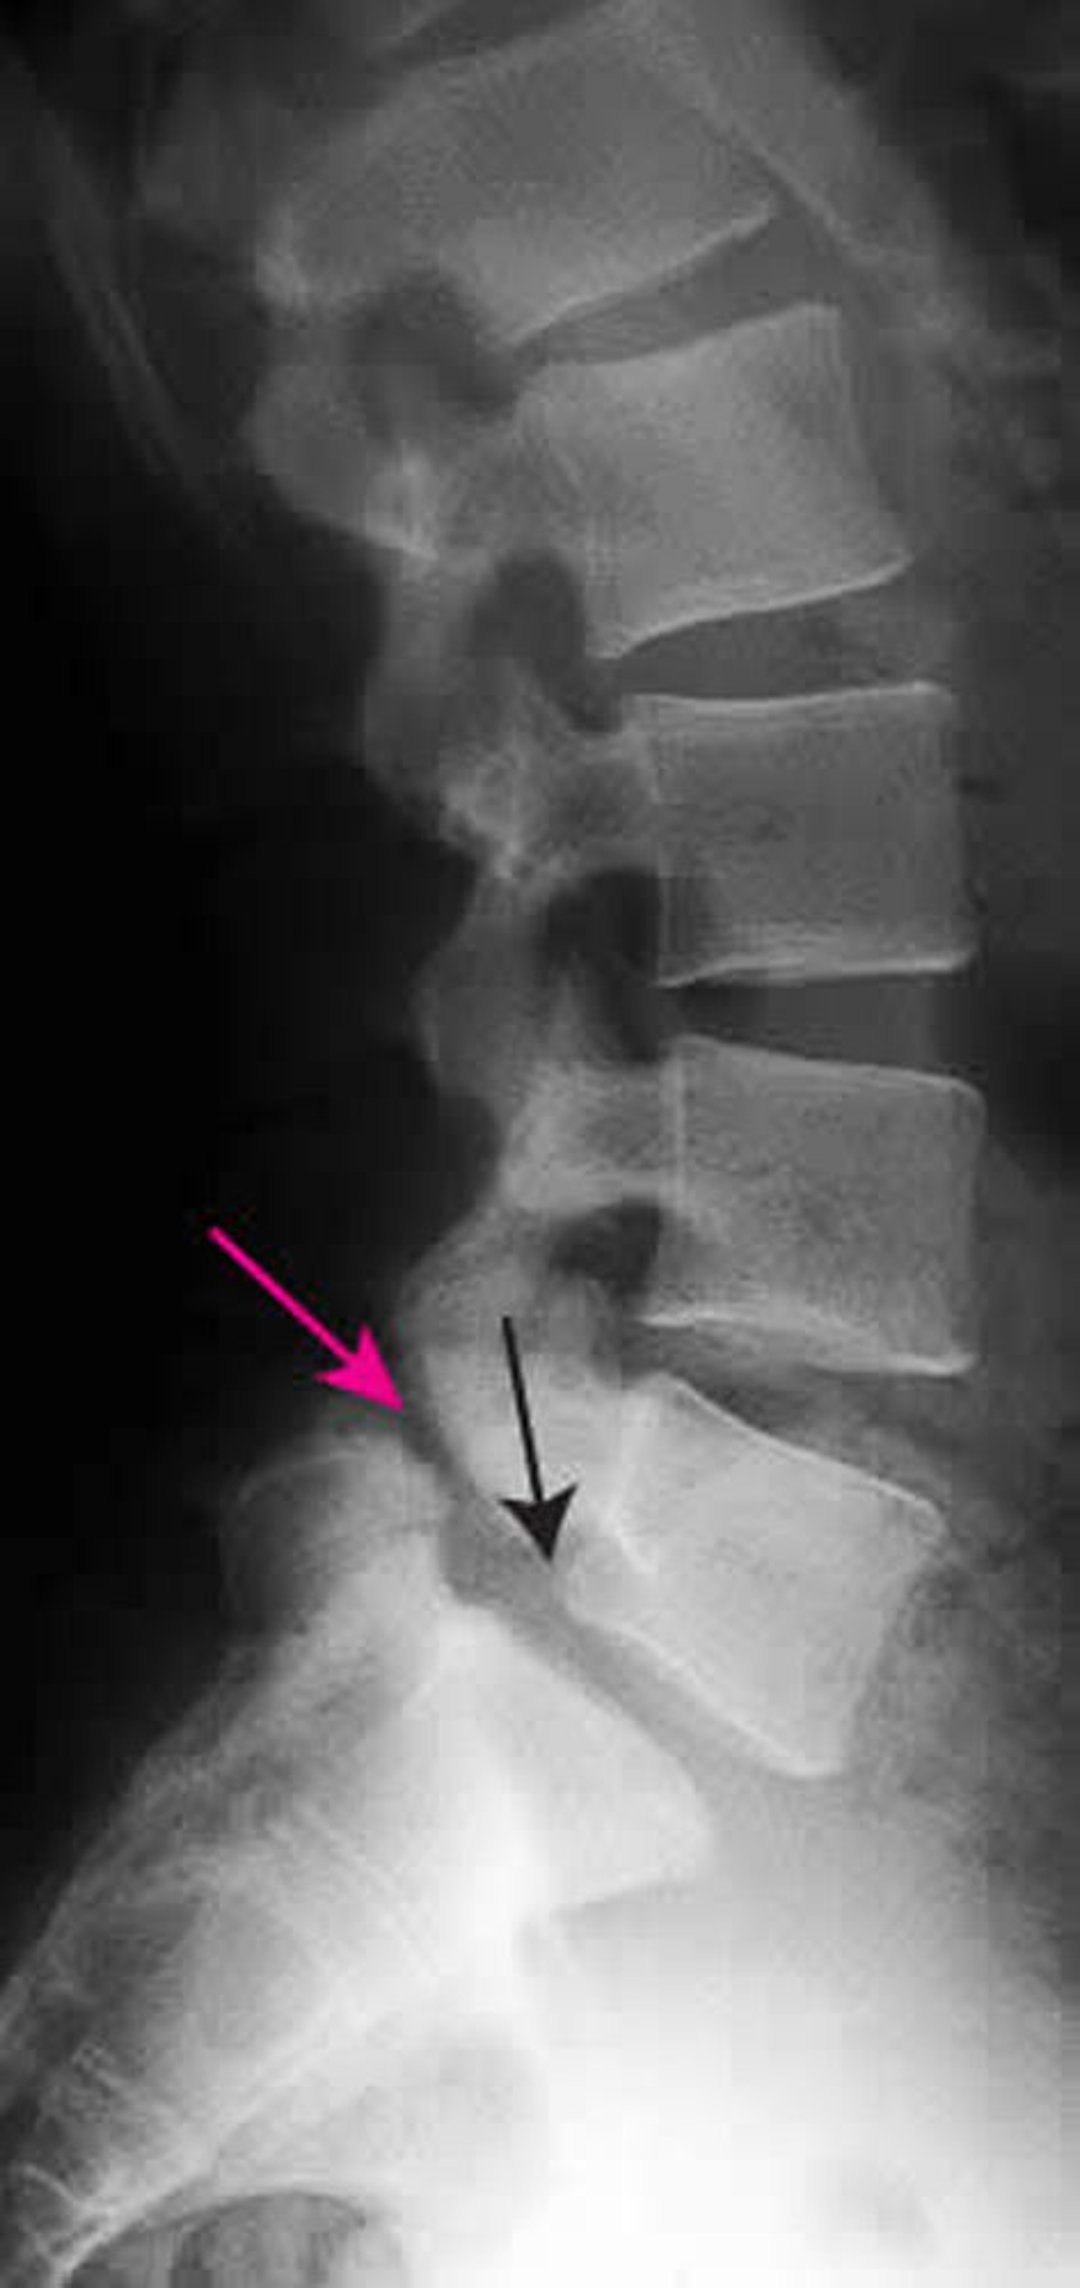

Espondilolistesis

Esta radiografía muestra espondilolistesis de grado 1 de L5 sobre S1. La flecha negra muestra el borde posterior de L5, que subluxa por delante de S1. La flecha roja señala la espondilólisis (defecto en la parte interarticular).